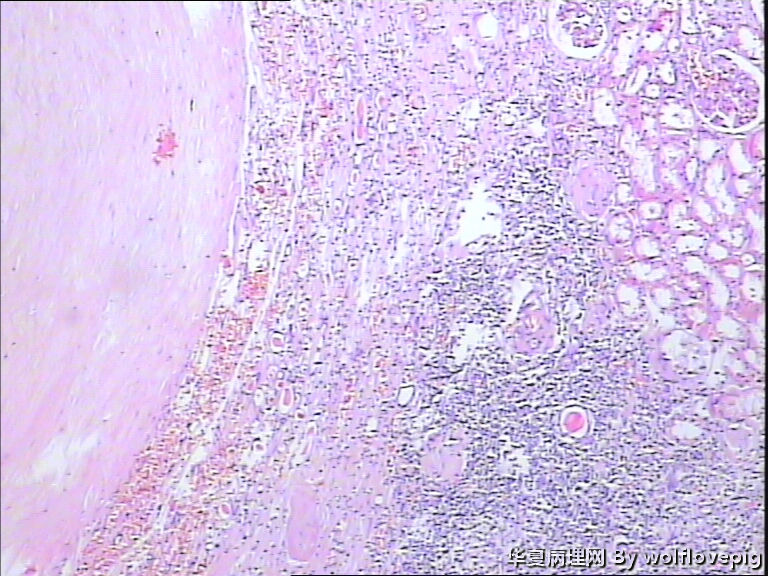

男,70y,左腰痛一年,反复血尿1月,坐肾区轻叩痛。

• 求助!肾脏包块!图2

图2

大体图片有些让人担心。镜下图片更倾向是良性病变。主要为对坏死组织的反应。

图片质量非常不好,显微镜下的图片几乎没法观察, 看大体标本还是不能除外肿瘤性病变,能不能采一些高质量的图片?

炎症性病变